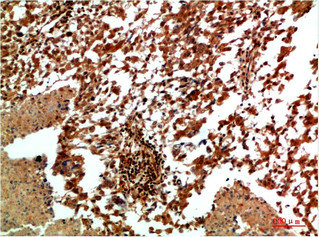

Immunohistochemical analysis of paraffin-embedded Human Lung Carcinoma Tissue using JNK2 Rabbit pAb diluted at 1:200